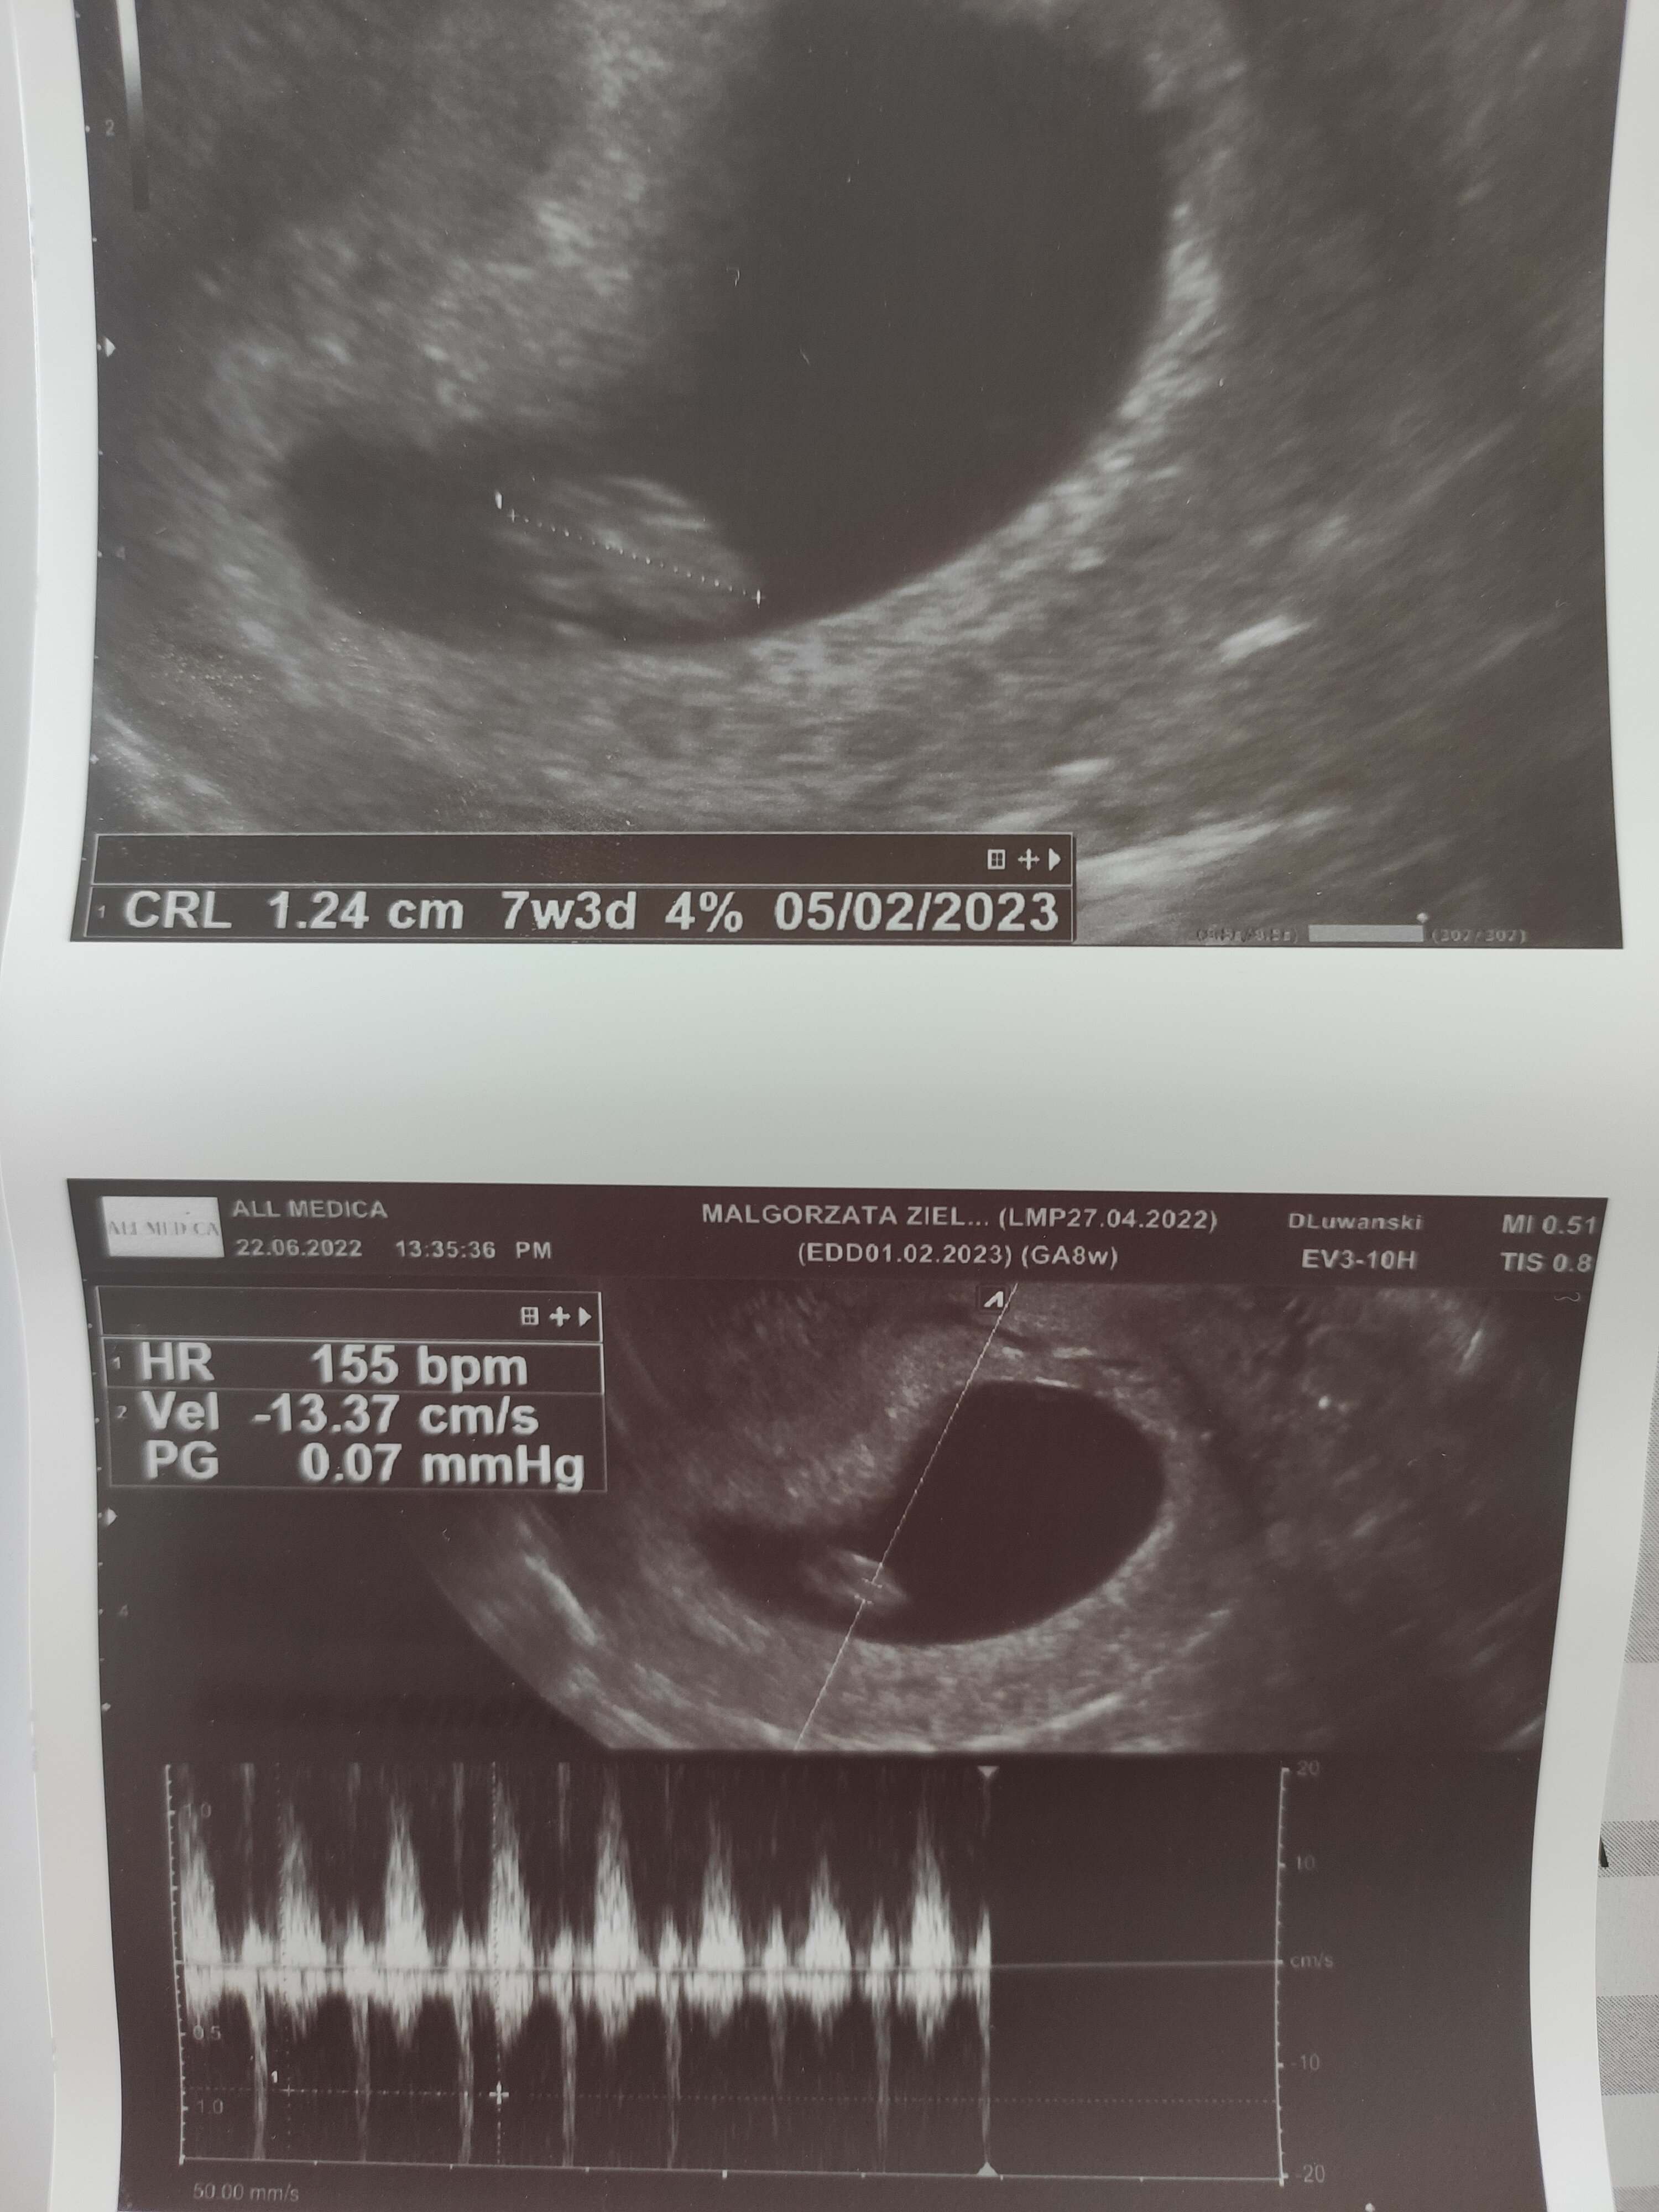

U mnie w 7+3 zarodek mial 1,24 cm i bilo serduszko, pierwsza wizyte mialam 5+3 to nie bylo nawet zarodka, puste jajo

• 16558993518004715558111761801252.jpg

16558993518004715558111761801252.jpg

1,3 MB · Wyświetleń: 57